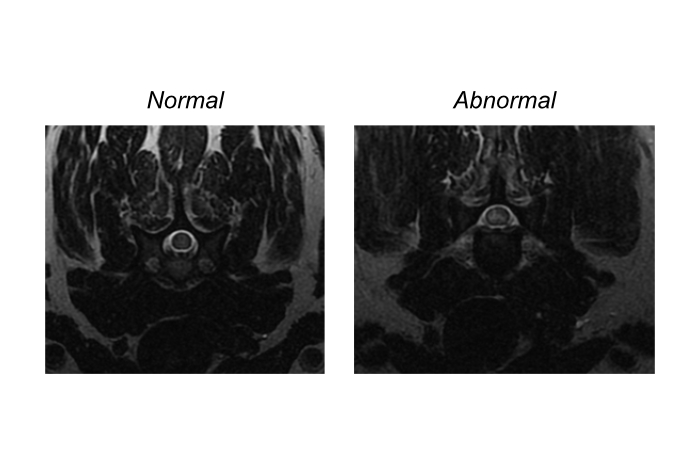

In the transverse T2-weighted images below, the patient’s normal spinal cord is visible in the left image and the lesion in the patient’s spinal cord is shown on the image on the right. The parenchyma of the normal spinal cord is relatively homogeneous and is slightly hyperintense to muscle. However, on the affected portion of the patient’s spinal cord, in the right image, you can see a marked hyperintensity that affects the right side of the spinal cord, predominantly the gray matter. (Reminder: MRI images are displayed with the patient’s right on the viewers left, and the patient’s left on the viewers right).